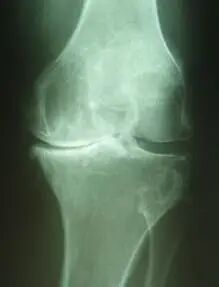

图1:该患者为左侧膝骨关节炎晚期,膝关节内翻畸形

有症状的患者,如果到医院检查的话,我们建议先做膝关节负重位X光片和髌骨屈曲30度轴位片,根据患者症状和照片分级情况,按照膝骨关节炎阶梯治疗方案治疗。